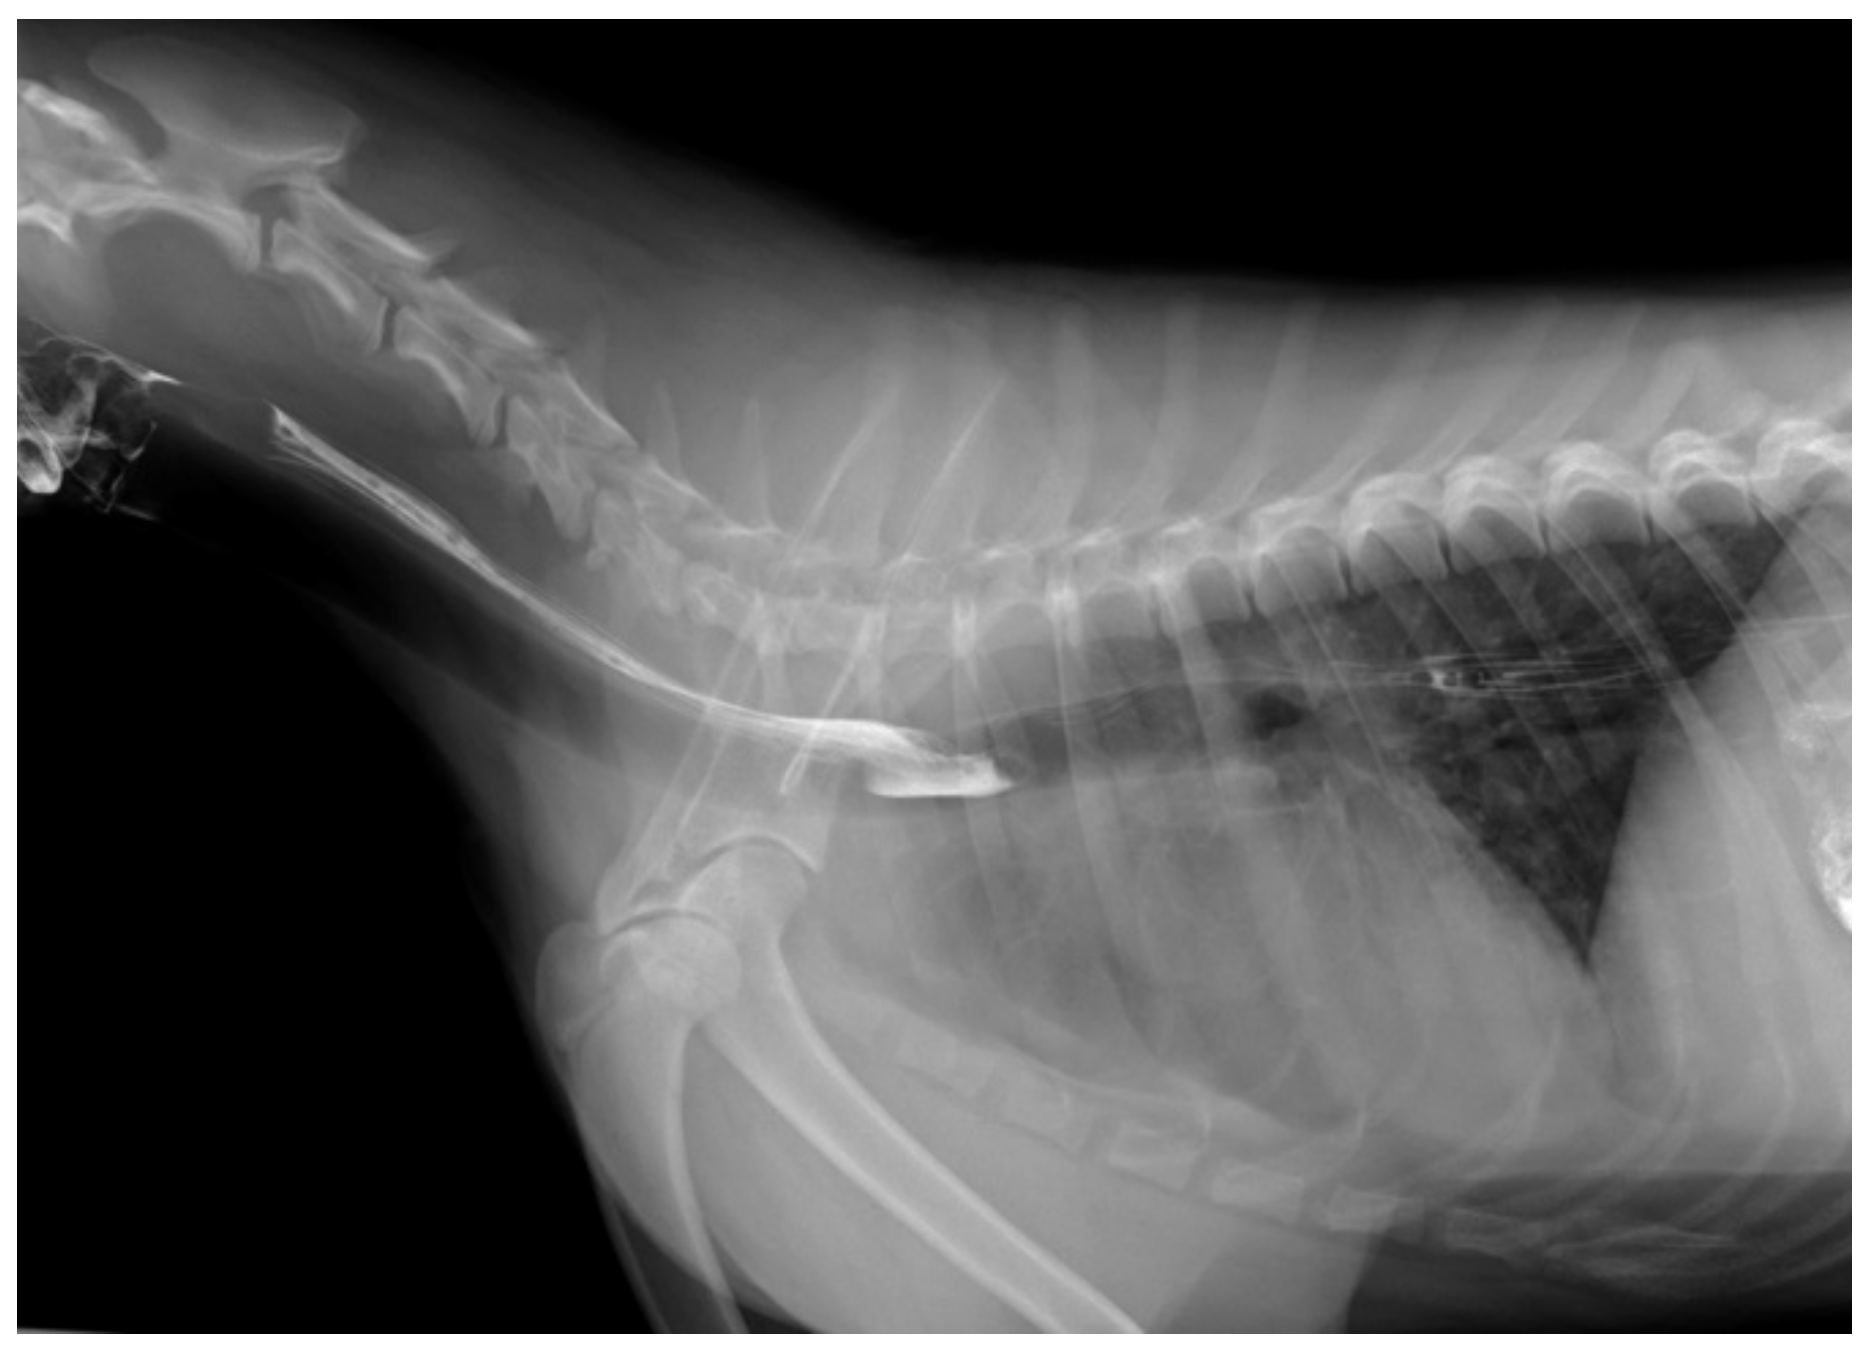

2. Case Presentation